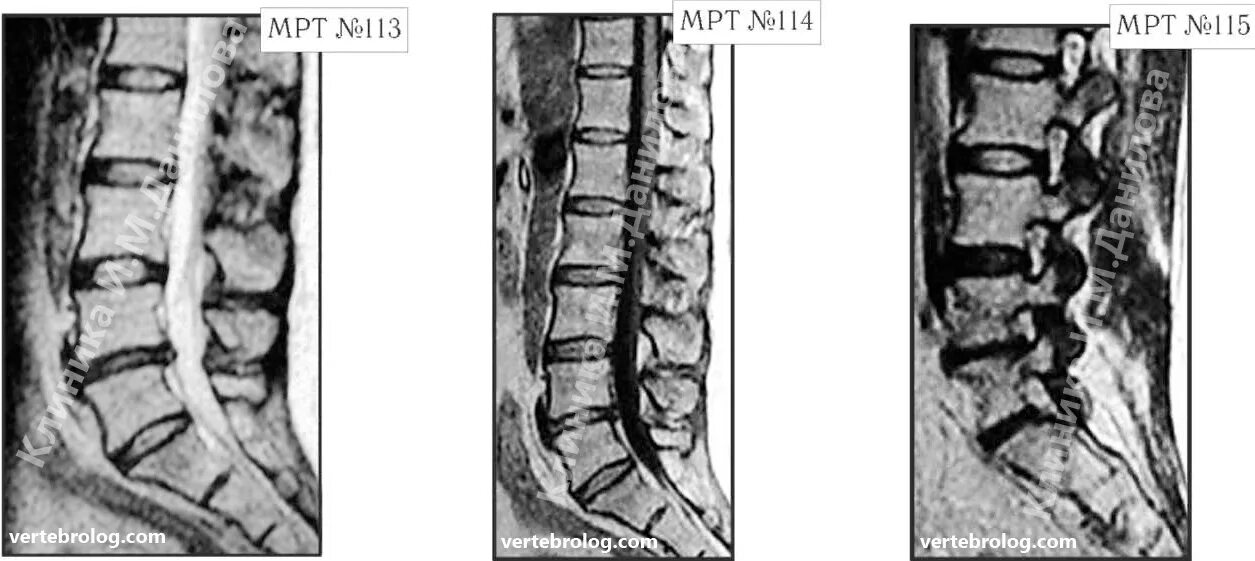

Грыжа дисков спондилоартроз